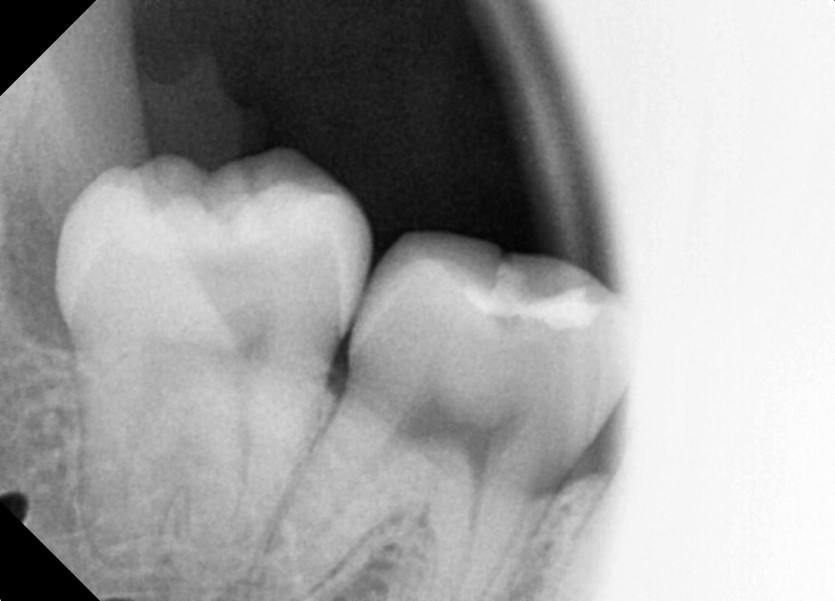

#18,48 사랑니 발치

구강 외과 전문의가 당일 발치했습니다.